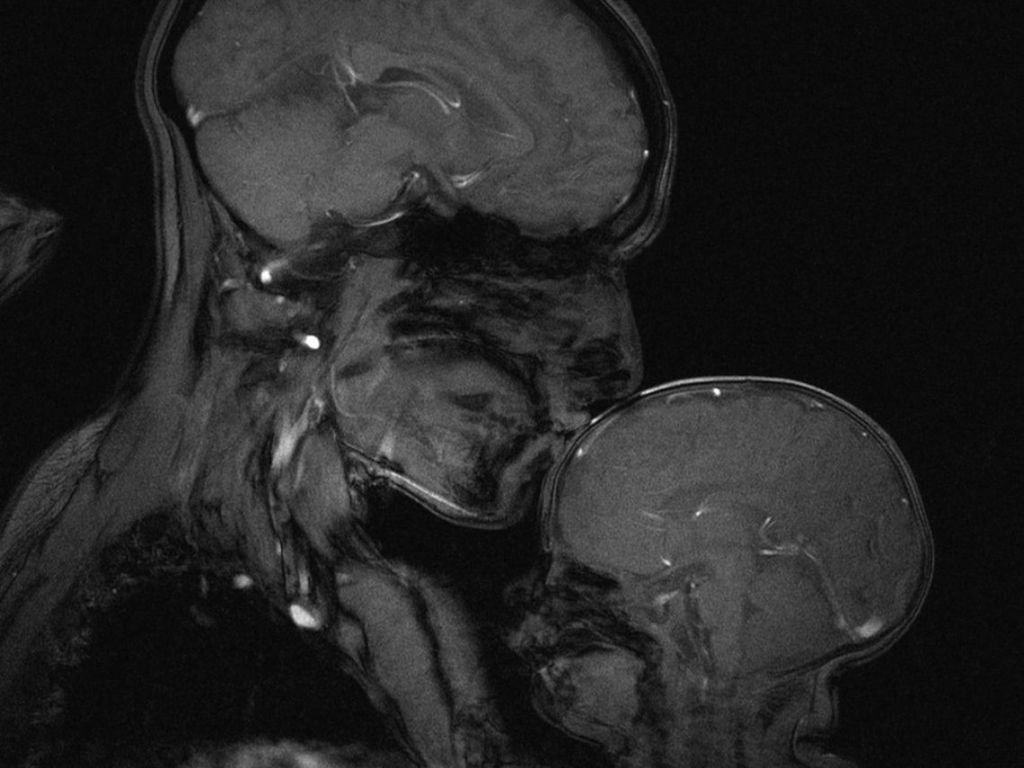

Además de este estudio, hace varios años se hizo famosa una resonancia que ya ha dado la vuelta al mundo y que sigue dando de qué hablar hoy en día. Es una resonancia en la que se puede ver la actividad del cerebro de una madre y en el de su hijo bebé cuando esta le está dando un tierno beso en la frente.

Los autores que están detrás de la imagen que ya ha dado la vuelta al mundo son Rebecca Saxe y Atsushi Takahashi, del Departamento del Cerebro y Ciencias Cognitivas del MIT, en Canadá. La autora en concreto ha concedido muchas entrevistas para hablar de todo lo que se puede ver en la imagen, pero una de las más transcendentales fue para Smithsonian, donde explicó que necesitó varios minutos, con total quietud por parte de los protagonistas para poder conseguirla.

Y la respuesta refleja uno de los mayores beneficios de besar a nuestros hijos mucho: la madre (de hecho esa madre que aparece en la foto es ella junto a su hijo). Su madre consiguió que, media el abrazo, el beso y su presencia, el bebé se estuviera quieto durante el tiempo que duró la resonancia. Además, afirmó que antes de esto, estaba llorando y que esas muestras de cariño materno no eran más que intentos de soluciones para clamar su llanto.

Aunque, de acuerdo a la autora, la imagen no fue tomada con ningún trasfondo científico, así que no podremos saber cuál fue la reacción del cerebro del bebé y de la madre a la hora del beso.